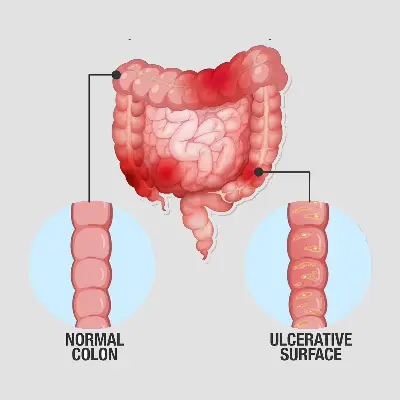

Gut

Altered gut microbiota, leading to digestive issues, nutrient absorption problems, and weakened immunity.

Our gut is our second brain.

Reducing stress, flourishes good gut bacteria, improving inflammation &digestive problems like IBS.

A healthy gut decreases cortisol levels.

The gut produces 90% of serotonin, vital for mood regulation and mental well-being.

Stress can trigger food sensitivities that didn’t exist before.